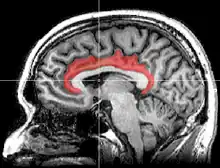

The cingulate cortex is a part of the brain situated in the medial aspect of the cerebral cortex. The cingulate cortex includes the entire cingulate gyrus, which lies immediately above the corpus callosum, and the continuation of this in the cingulate sulcus. The cingulate cortex is usually considered part of the limbic lobe.

Medial surface of left cerebral hemisphere, with cingulate gyrus and cingulate sulcus highlighted. | |